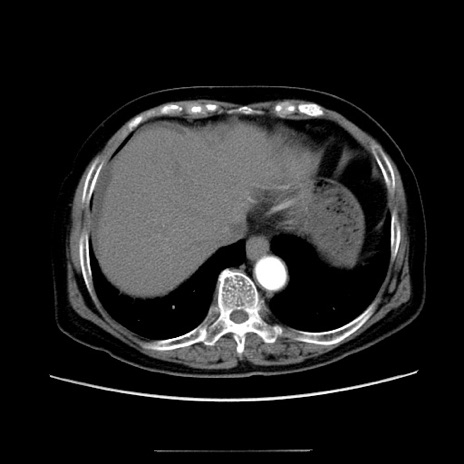

冠状断像

【症例】70歳代女性

【主訴】お腹が張る

【現病歴】1週間くらい前から腹部膨満の自覚あり。昨日夜から増悪したため、本日救急外来受診。

【身体所見】意識清明、BT 36.5℃、BP 165/106mmHg、HR 80bpm、SpO2 98%、腹部:膨満、軟、自発痛・圧痛なし、触診にて不快感あり、腸蠕動音:減弱

【データ】WBC 12600、CRP 1.04